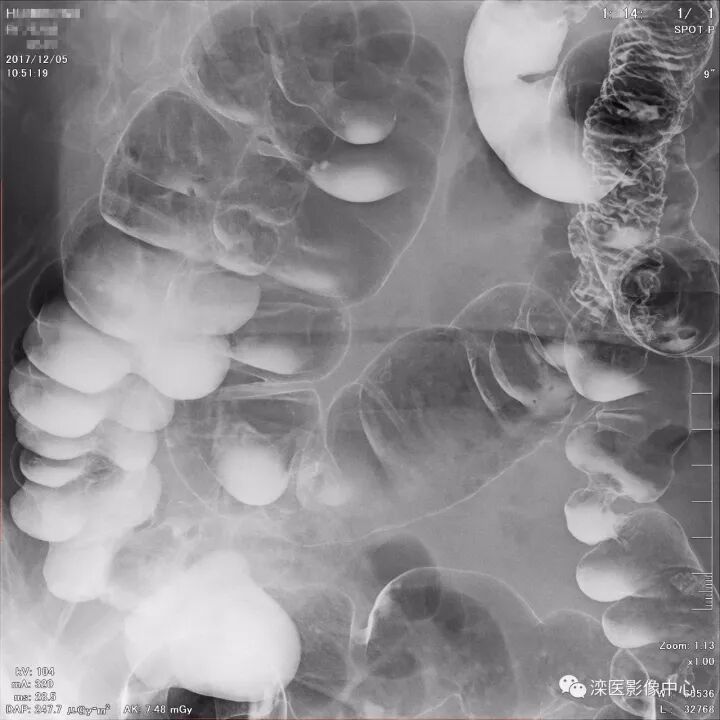

下面请您审阅近期我院影像科开展下消化道双对比造影检查的图像:

(俯卧位观察直肠、乙状结肠及降结肠)